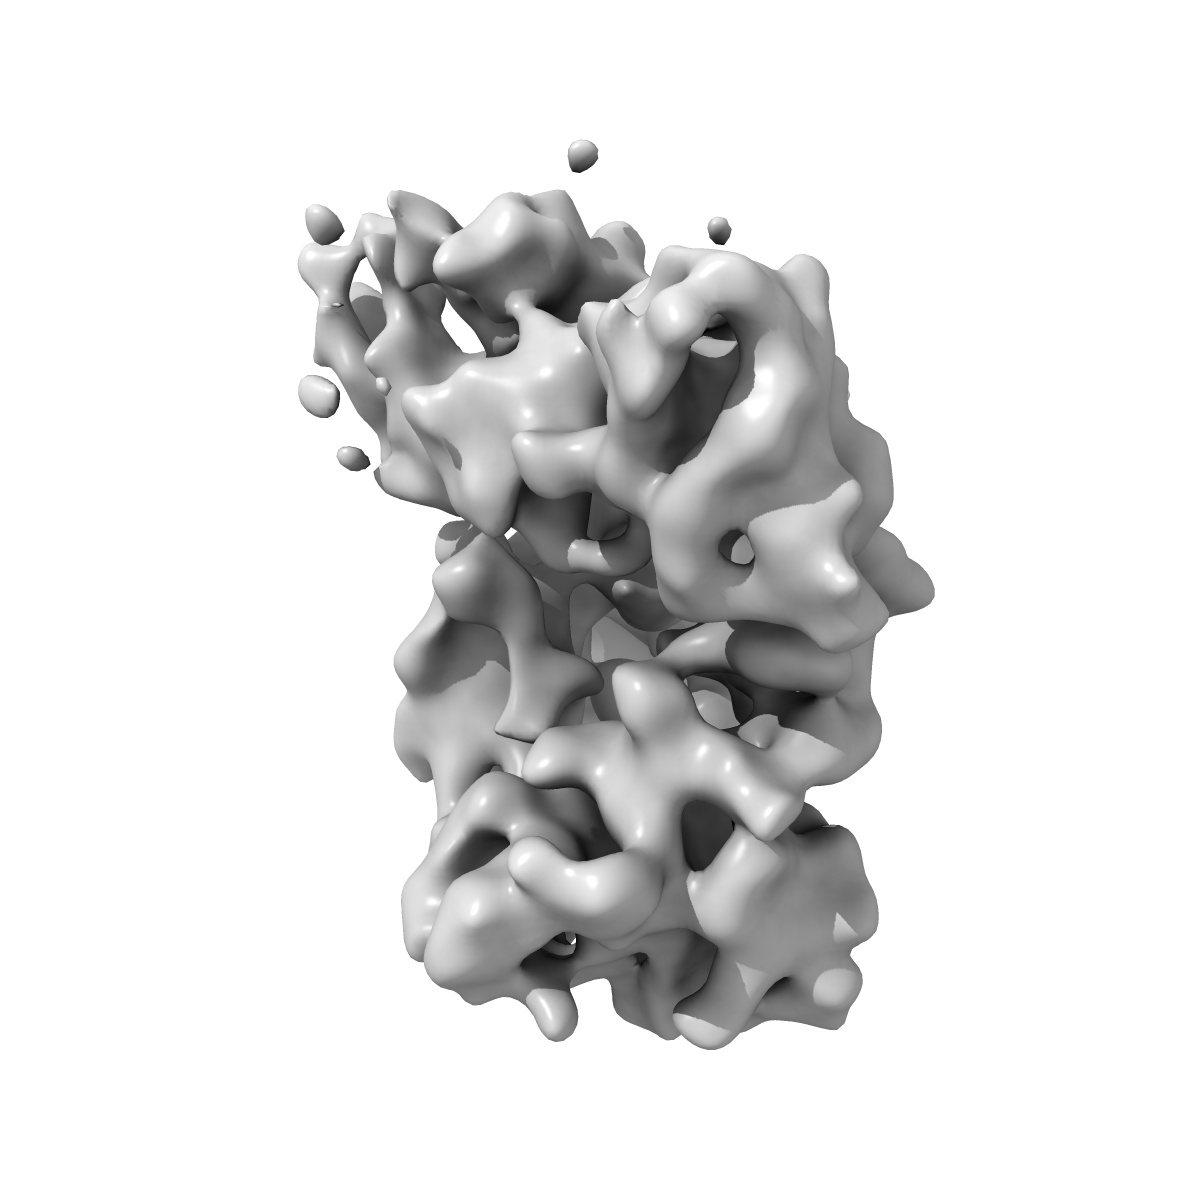

Structure of a partially disrupted IgE high affinity receptor complex bound to an omalizumab variant

Sample: Locked complex of IgE-Fc (G335C) and alpha chain of the high affinity IgE receptor (W156C) bound to clone_7 scFV

Directed evolution of and structural insights into antibody-mediated disruption of a stable receptor-ligand complex.

Pennington LF , Gasser P , Kleinboelting S , Zhang C, Skiniotis G , Eggel A , Jardetzky TS

(2021) Nat Commun , 12 , 7069 - 7069